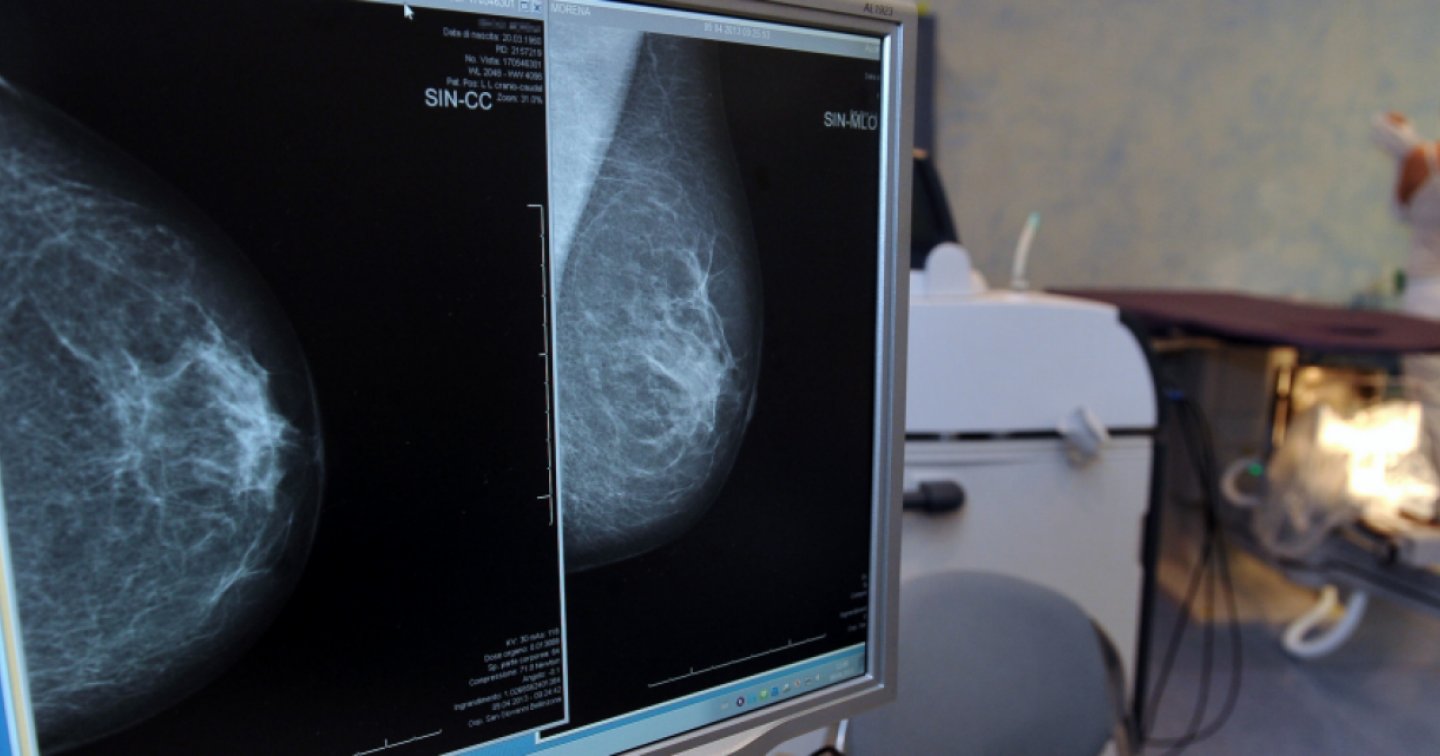

"Un segnale allarmante", ha detto senza mezzi termini, spiegando che per tumori giovanili si intendono quelli insorti in persone con meno di 50 anni, che prima erano rari. In particolare, si ravvisa una maggior incidenza di quelli al seno, al colon, al pancreas, al fegato, alla prostata, ai reni e all'utero. Aumentano anche quelli tra gli over 65, da collegare però alla maggior speranza di vita.